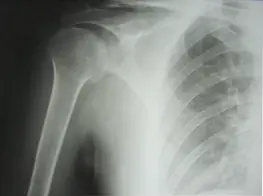

Fracture de l’extremite superieure de l’humerus